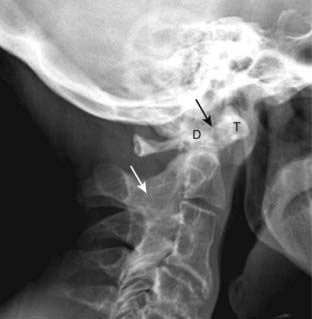

Figure 23-15 Rheumatoid arthritis of the cervical spine.

RA tends to involve the cervical spine by producing ligamentous laxity, which can lead to forward subluxation of C1 on C2 (atlantoaxial subluxation). The distance between the anterior border of the dens (D) and the posterior border of the anterior tubercle of C1 (T) is called the predentate space and is normally no more than 3 mm. This patient’s predentate space measured 8 mm (solid black arrow). RA may also cause fusion of the facet joints (solid white arrow).